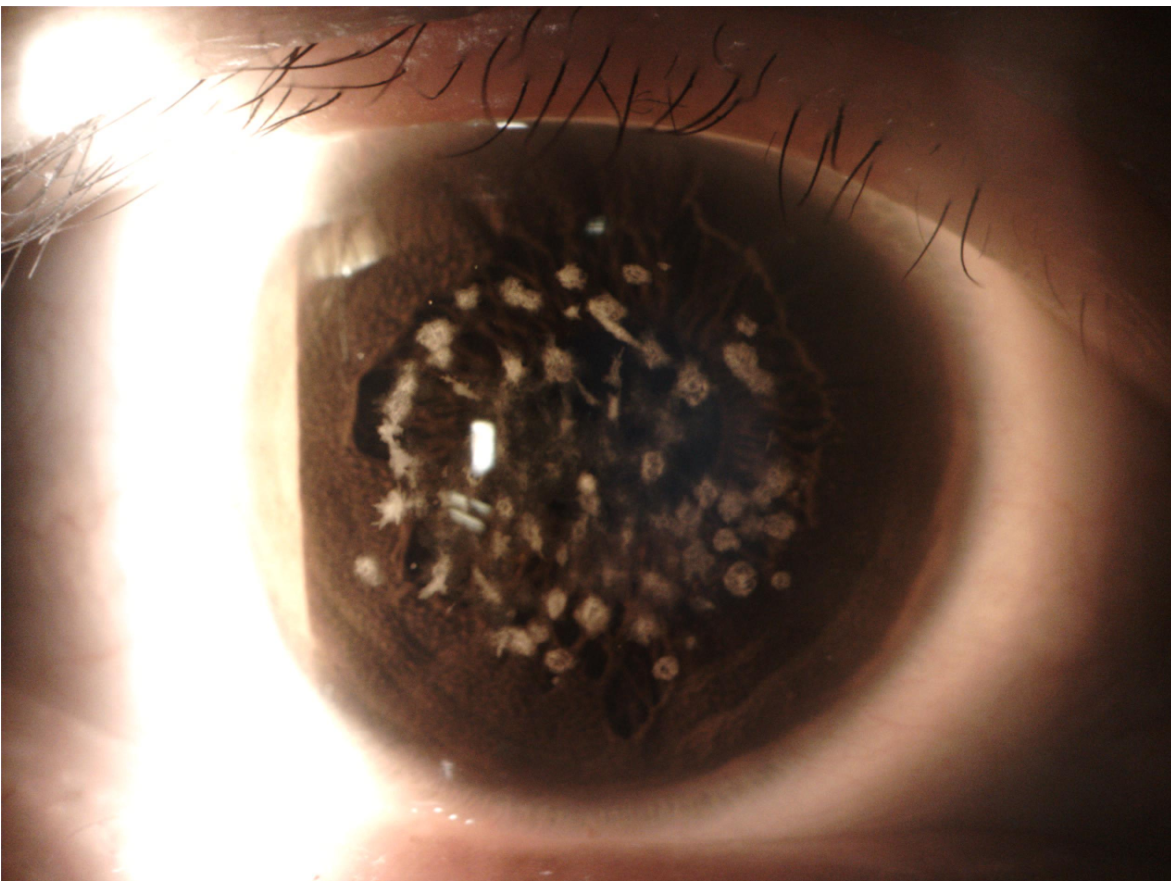

裂隙灯图:

裂隙灯图(Slit Lamp Photography):

- 用途: 裂隙灯是一种眼科设备,通过强光束来检查眼睛前部结构,如角膜、虹膜、晶状体和前房。

- 优点: 裂隙灯摄影对于发现和诊断角膜划伤、干眼症、白内障和青光眼等前段眼部疾病非常重要,并且能够记录治疗前后的变化。